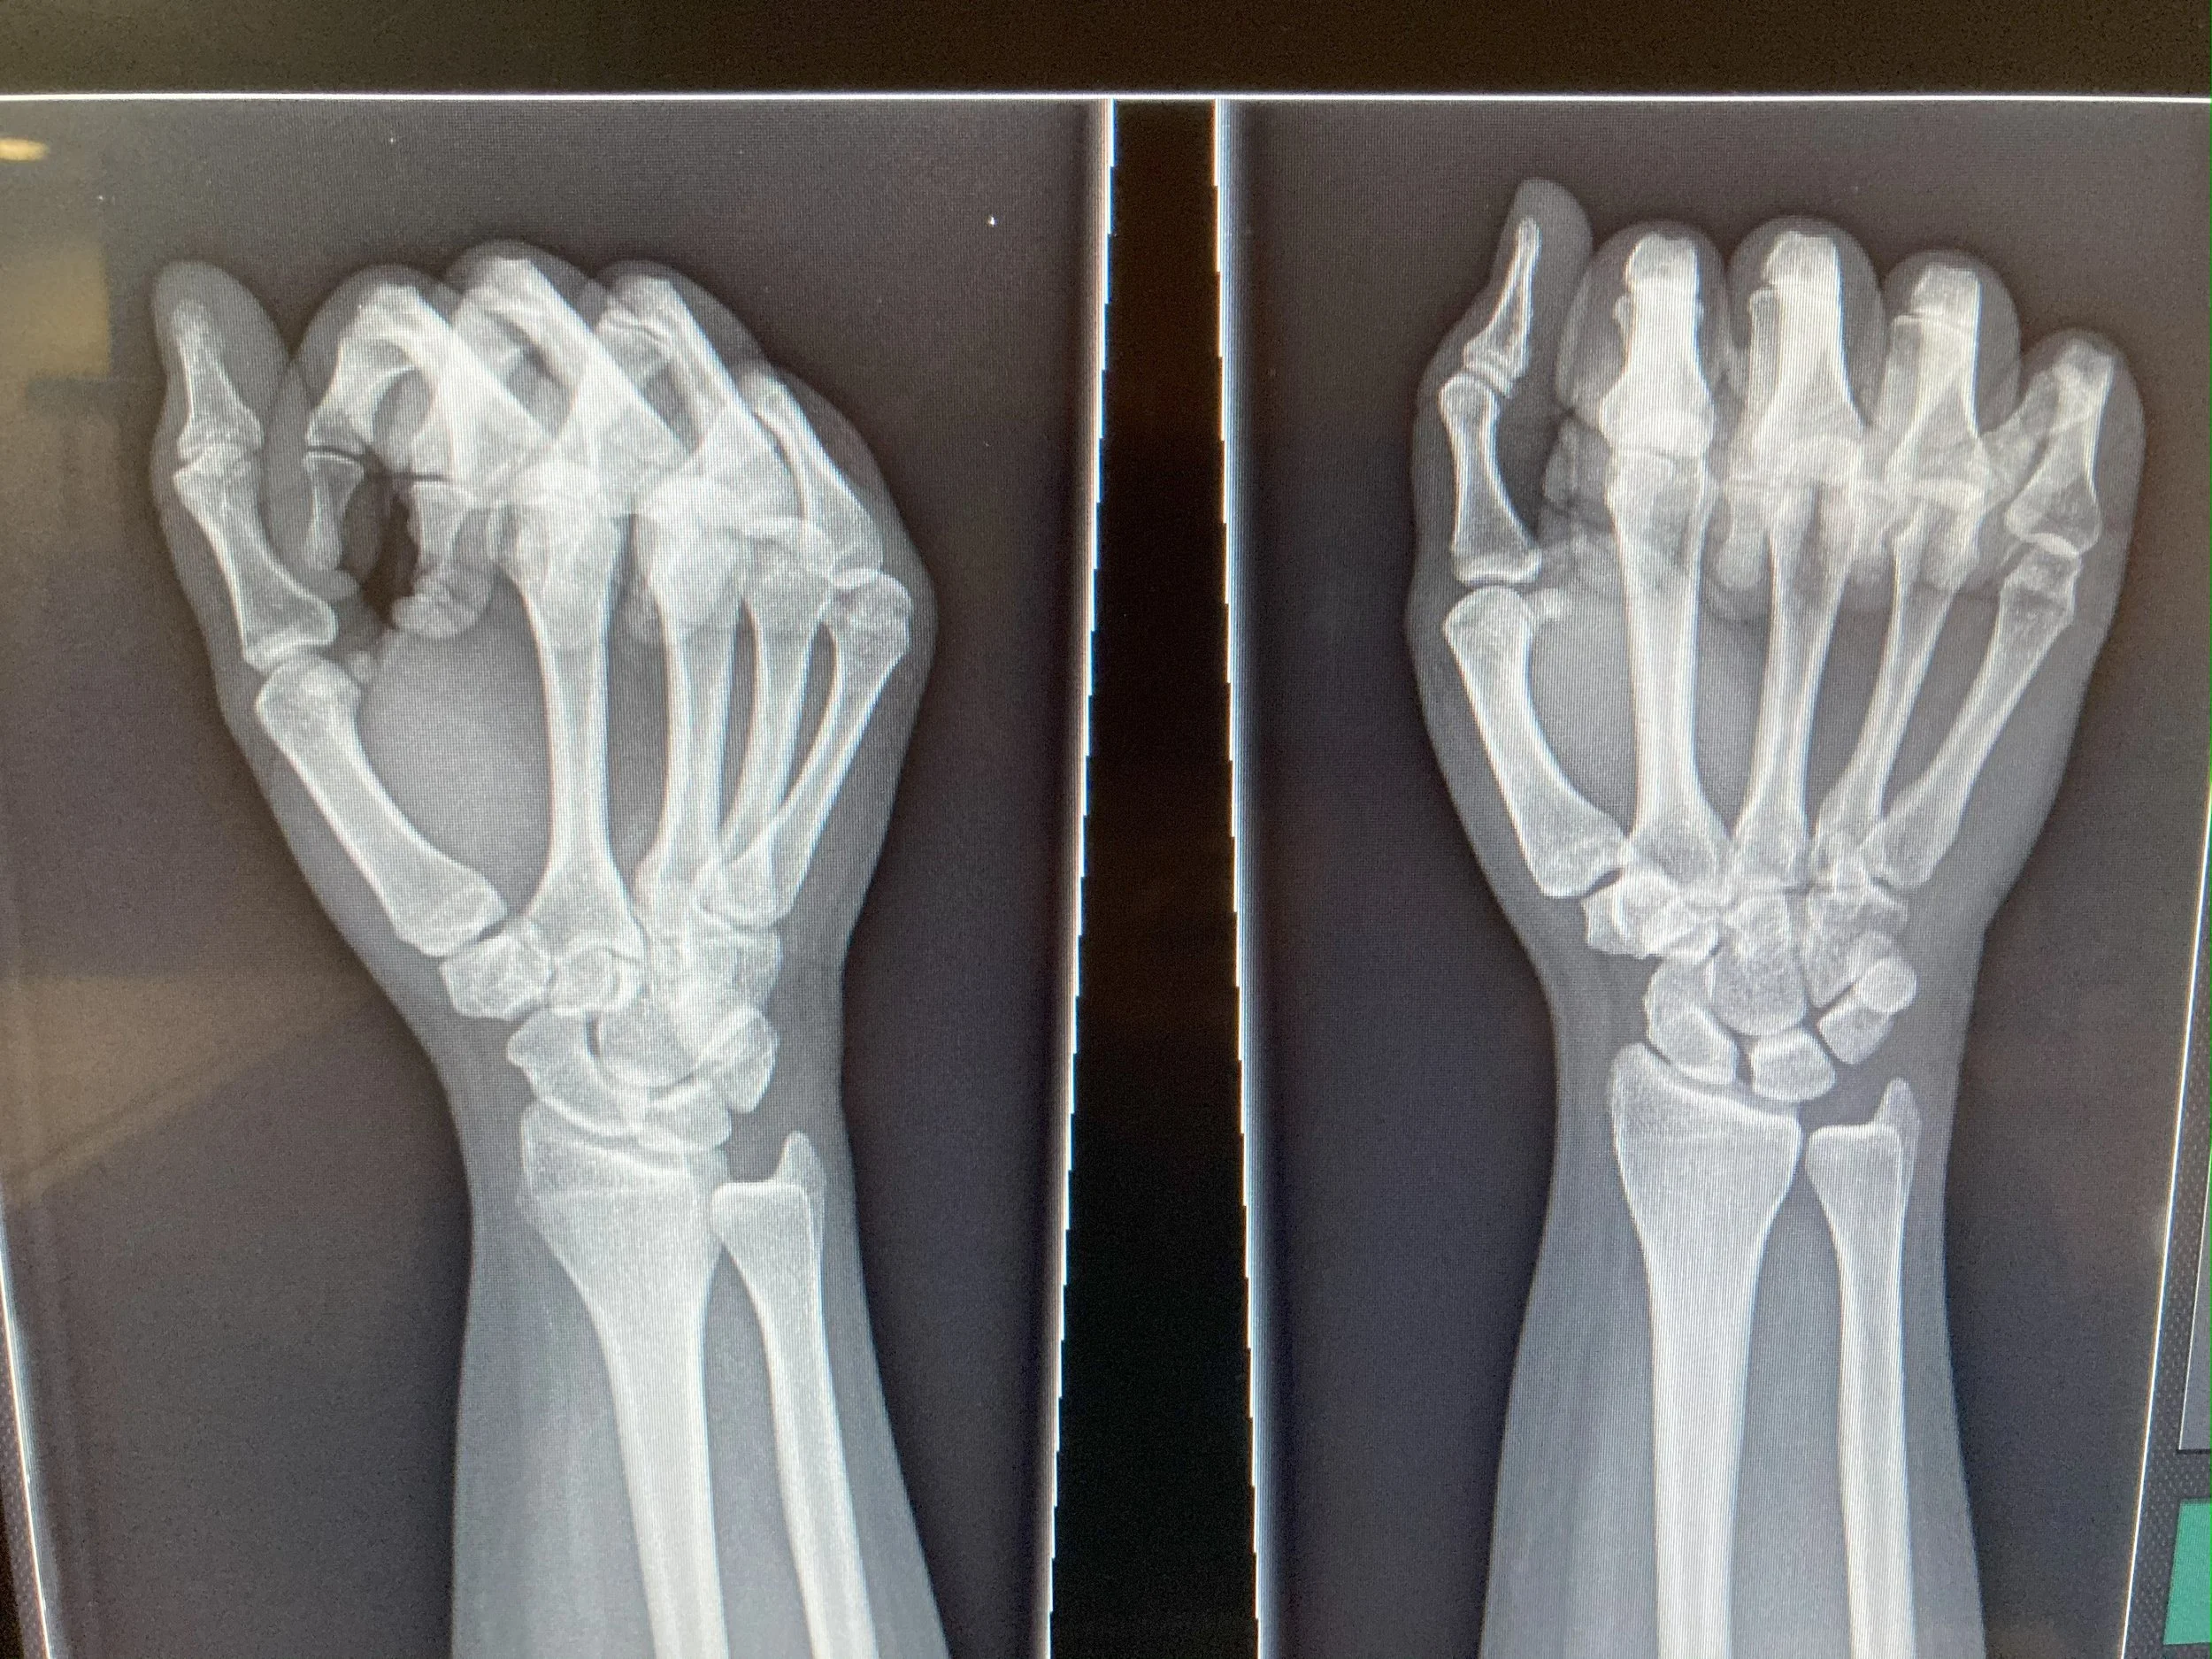

X-ray images of two hands, showing bones.